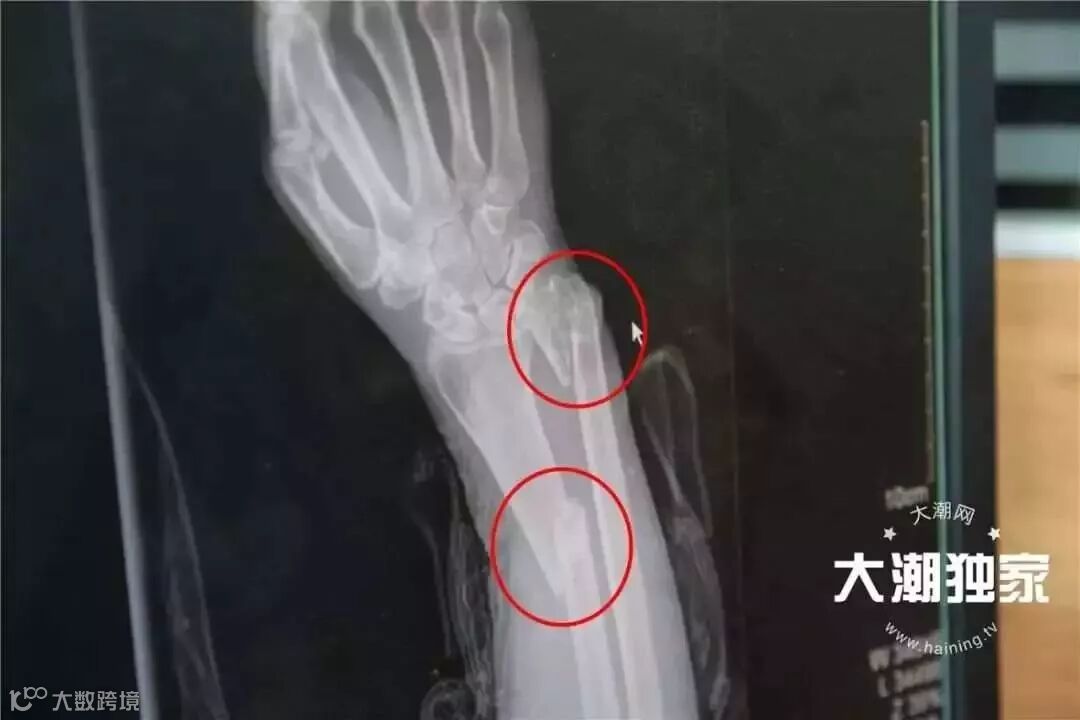

老太当时右手腕有点骨折

不过额头有6-7公分伤口

右手前臂外侧有1-2公分伤口

右前臂有2处骨折